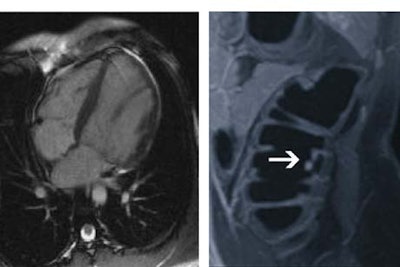

| Left, mitral-valve prolapse is discovered in a 57-year-old male patient during cardiac MRI portion of whole-body screening exam. Right, an unsuspected colorectal polyp is seen in a 49-year-old female patient during colorectal phase of whole-body screening. Images courtesy of Dr. Thomas Lauenstein. |